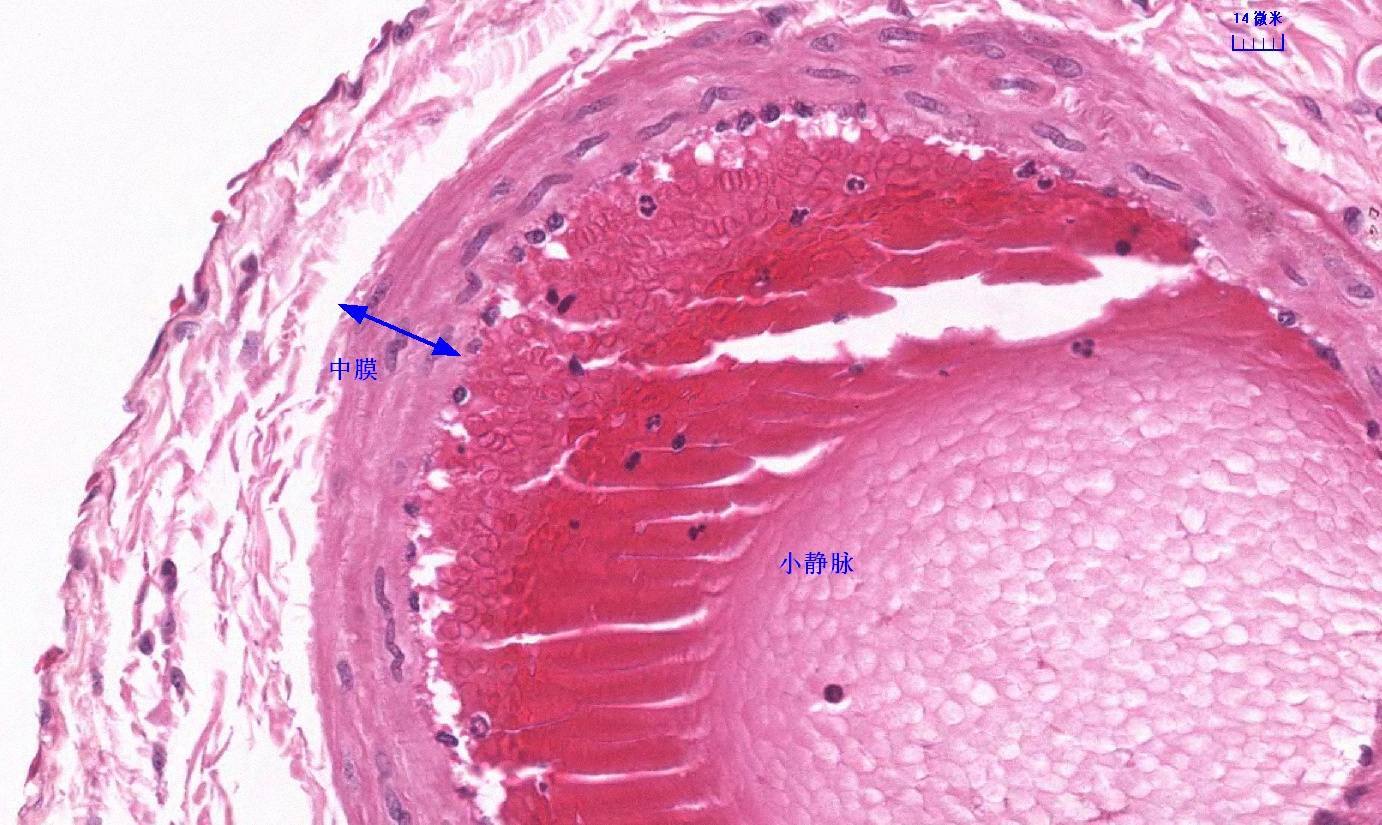

6.1 循环系统切片库